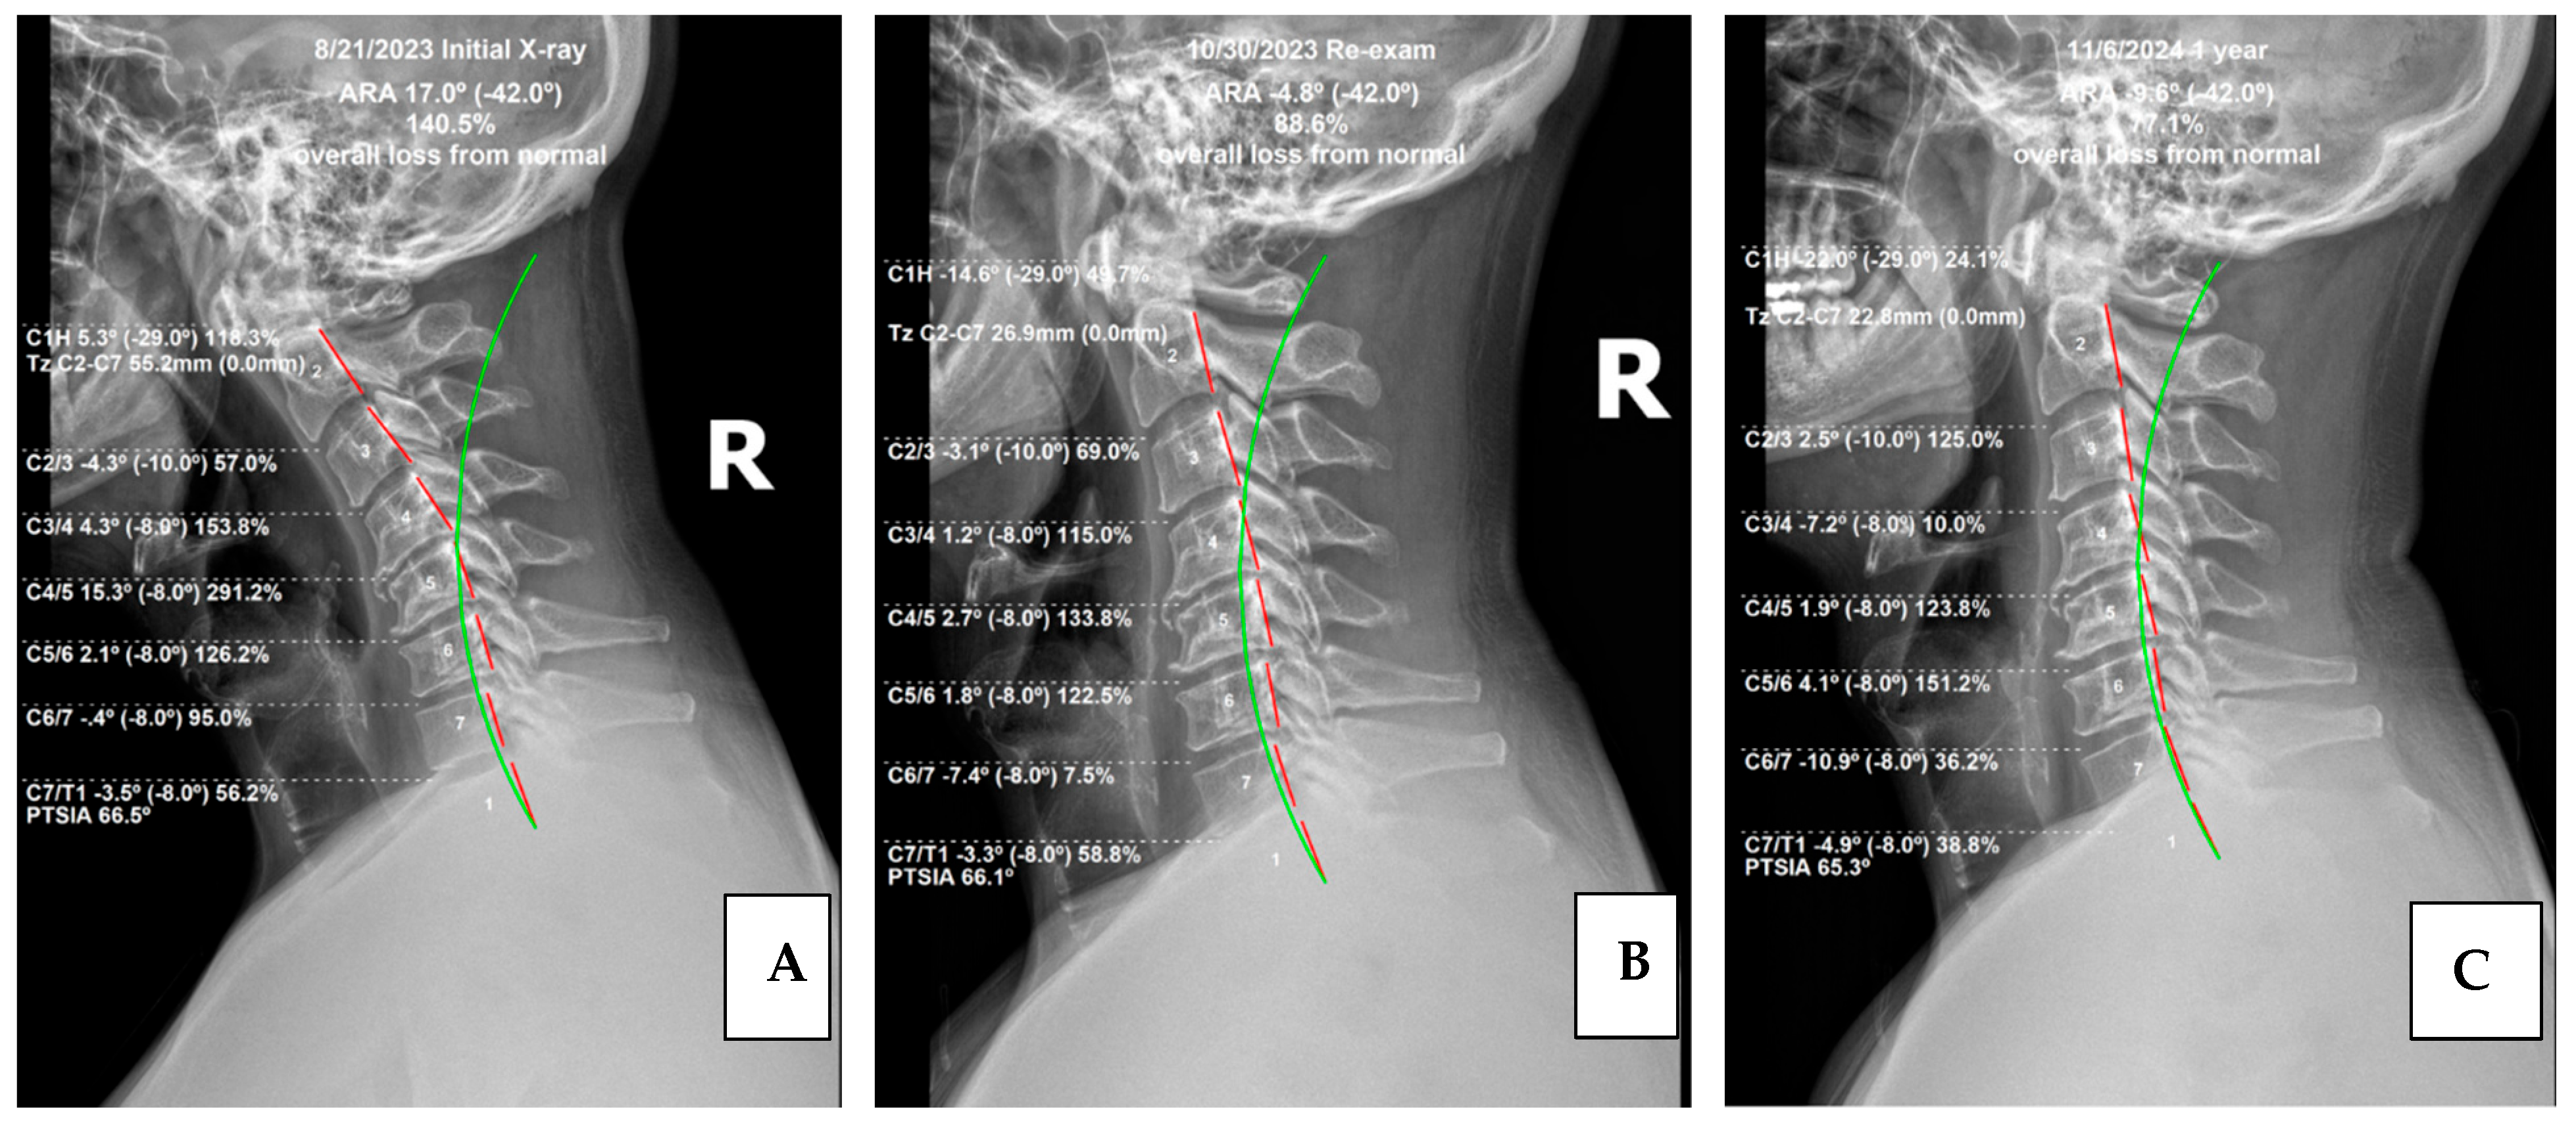

The measurement of the cervical spine absolute rotation angles (ARA C2–C7) was found to be 17°, compared to the normal measurement of −42°, using the Harrison posterior tangent method (HPTM) (Figure 1) [11]. The kyphotic apex was at C4/5, where the segmental rotation angle (SRA) measured 15.3° compared to the normal value of −8°. This is a 291.2% loss of segmental cervical lordosis. Anterior translation of the head measured 55.2 mm, whereas the normal measurement is 0 mm.

Like the initial radiographs, all films were measured digitally using PostureRay® software. Notably the patient achieved improvement relative to cervical lordosis. The cervical curve (C2–7) improved from 17.0° (kyphosis) to −4.8° (global lordosis), a 22° change. This exceeds the findings of Oakley et al. in a 2021 study which reviewed results of CBP® cervical spine rehabilitative cases, which found an average 14° change [24]. Also of interest, the measured forward head posture (FHP) reduced from 55.2 mm to 26.9 mm. This 28.3 mm decrease also exceeded the results of the previously mentioned study, which found an average of 11.9 mm.

While absolute changes were significant, segmental changes showed important and remarkable improvements. The initial radiographic measurement of the segmental rotation of C3/4 (4.3°) was reduced to 1.2°, notably decreasing segmental kyphosis. Even more significantly, C4/5 decreased from 15.3° to 2.7°. Finally, C6/7 increased lordosis from −0.4° to −7.4°, showing numerically significant improvement (Figure 4).

Of interest, the radiographic findings continued to improve to a significant degree, suggesting the importance of patient compliance with home care and stabilization care. This continued improvement reinforces established principles of ligament remodeling alongside principles of viscoelastic creep/relaxation [26,27]. Mensuration of the cervical spine showed the absolute rotation angle of the cervical spine (ARA) or cervical lordosis using the HPTM. Post-treatment ARA measured −4.8°, while re-evaluation at 13 months measured −9.6°, bolstering the value and necessity of monthly maintenance care. Mathematically this patient has transitioned from global cervical kyphosis to global cervical lordosis. This is noteworthy, as cervical kyphosis has technically been described in the literature as a deformity, with this case meeting the criteria for a specific classification, which is beyond the scope of this case report [28].

On a more granular level, segmental values also showed marked improvement in cervical lordosis. C3/4 improved dramatically from 1.2° (kyphosis) to −7.2° (lordosis). C5/6 showed noteworthy change as well: 1.8° to −8.0°. FHP improved as well, measuring 26.9 mm in the previous exam and measuring 22.8 mm at follow-up. Finally, the thoracic spine ARA also showed a 25% improvement in kyphosis, increasing from 37.1° to 46.4°, with 44° being normal (Figure 5).

Figure 4. Lateral cervical radiographs. Image (A) is the initial radiograph. Image (B) is the post-treatment radiograph. Image (C) is the one-year follow-up. The broken red line represents the HPTM analysis of the posterior body margin of the individual cervical vertebrae. The green line represents the ideal model of cervical lordosis for comparison of the patient’s measurements relative to normal measurements. These images were measured and digitized using PostureRay® analysis software.